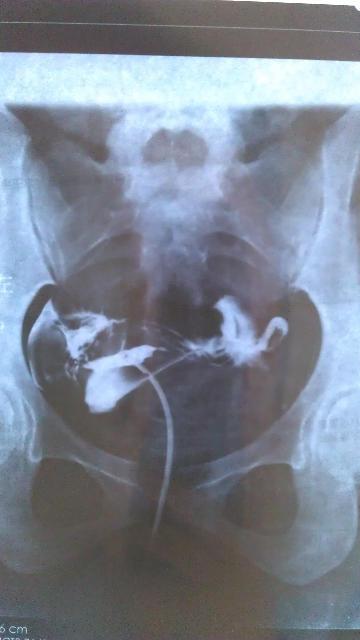

患者信息:女 28岁 病情描述(发病时间、主要症状等):表现:注入造影剂后,宫腔充盈,子宫影大致呈三角形位置偏左,边缘光滑。两宫角充盈可, 双侧输卵管在宫旁连续显示,边缘光滑,造影剂经双侧伞端溢入盆腔,并可见少许弥散。第三张片显示盆腔内见有游离造影剂。诊断:子宫影显示正常,双侧输卵管通畅。 本人月经正常,周期27-28天,卵泡监测排卵正常,大小在2.0*1.9左右想得到怎样的帮助:结婚一年一直没有宝宝,去医院做造影后说我盆内输卵管有粘连,医生让我住院治疗两个疗程,我只住院治疗一个疗程,这个月不想去了,我找人说先让我先吃两瓶八珍益母丸,请问看片子我是否还要住院?我是否可以要宝宝了曾经治疗情况及是否有过敏、遗传病史:无